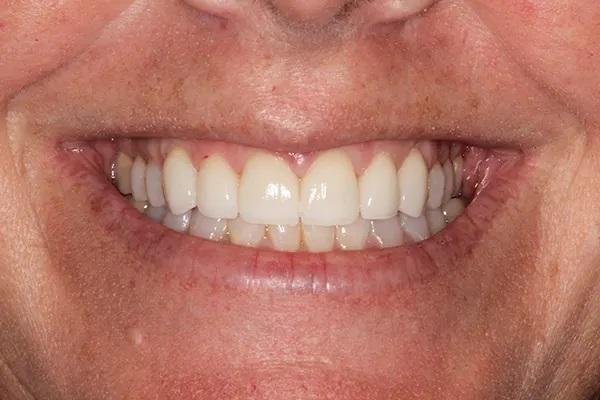

Для постоянной фиксации виниров использовался полупрозрачный цемент (RelyX Veneer Cement, 3M Oral Care) виниры были зафиксированы парами начиная с области центральных резцов, затем латеральные резцы и заканчивая клыками. Каждую реставрацию закрепляли с помощью 3-секундного светового отверждения, а излишки цемента удаляли с помощью ультразвукового скеллера. Окончательное отверждение осуществлялось путем полимерезации светом в течение дополнительных 20 секунд на каждый зуб. Результаты проведённого лечения показаны на фото с 9 по 12. Изменение улыбки пациентки с фиксированными постоянными реставрациями (фото 9). Демонстрация смыкания после лечения (фото 10). Портретная фотография анфас с широкой улыбкой (фото 11). Прицельные снимки зубов пациентки после проведенного лечения (фото 12).

Фото 9

Фото 10